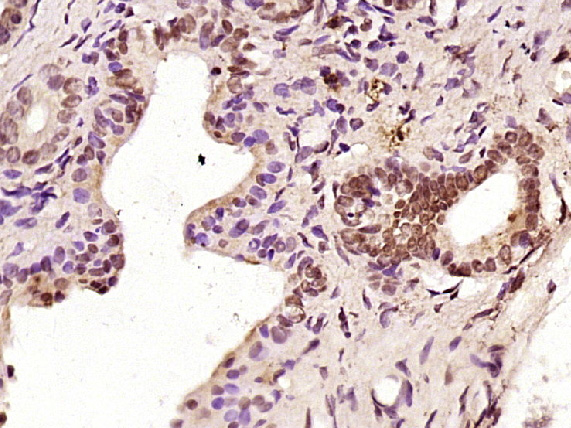

Paraformaldehyde-fixed, paraffin embedded (Mouse placenta); Antigen retrieval by boiling in sodium citrate buffer (pH6.0) for 15min; Block endogenous peroxidase by 3% hydrogen peroxide for 20 minutes; Blocking buffer (normal goat serum) at 37°C for 30min; Antibody incubation with (C-REL) Polyclonal Antibody, Unconjugated (bs-2666R) at 1:400 overnight at 4°C, followed by operating according to SP Kit(Rabbit) (sp-0023) instructionsand DAB staining.

Paraformaldehyde-fixed, paraffin embedded (Rat pancreas); Antigen retrieval by boiling in sodium citrate buffer (pH6.0) for 15min; Block endogenous peroxidase by 3% hydrogen peroxide for 20 minutes; Blocking buffer (normal goat serum) at 37°C for 30min; Antibody incubation with (C-REL) Polyclonal Antibody, Unconjugated (bs-2666R) at 1:400 overnight at 4°C, followed by operating according to SP Kit(Rabbit) (sp-0023) instructionsand DAB staining.